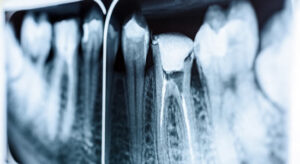

Why Choose Newport Smile Studio For Your Next Crown

At Newport Smile Studio, Dr. Etemad believes in using the latest technology available to make it easier on our patients. We have partnered with Itero Scanner for all of our crown impressions.

Instead of taking a gooey impression which can be very time consuming and uncomfortable, The Gentle Dentist of Newport Beach, Dr. Abrak Etemad uses the Itero Scanner to scan your teeth. This is much easier, faster and more accurate to fabricate your crown.

What kind of Crowns does Newport Smile Studio perform?

At Newport Smile Studio, we believe in highest quality of work, as a result we only fabricate high quality zirconia crowns. We do not believe in cheaper crowns such as PFM (Porcelain Fused to Metal). Even though they last long like zirconia crowns but they are prone to fracture as two material fused together mental to porcelain. PFM’s are not esthetic and also cause gum recession over time.